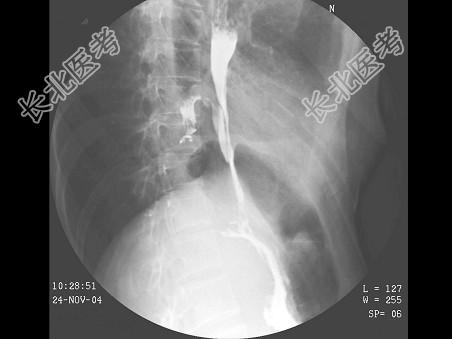

- 单项选择题女,39岁, 左下肺叶切除术后。体检:左下肺呼吸音弱, 行胸腔闭式引流术,引流出脓性分泌物。结合图像, 最可能的诊断为 ( )

E、食管下段胸腔瘘